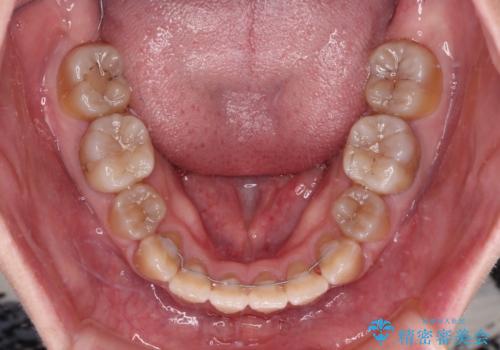

八重歯とクロスバイト 目立たないワイヤー装置での抜歯矯正

- 八重歯や前歯のデコボコを気にして来院された患者様です。

歯列が前方に傾斜しており、デコボコが強かったため、上下左右第一小臼歯4歯を抜去し、ワイヤー装置による矯正治療を行うこととしました。

上下の正中がずれていましたが、抜歯矯正であったので、極力正中位置を合わせるように治療を進めて行きました。

顎間ゴムの使用などにより、正中位置を改善することができました。